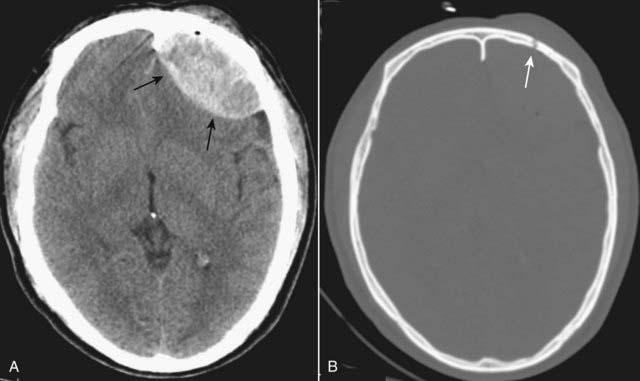

image Recognizing traumatic intracerebral hemorrhage on CT

Cerebral contusions may appear as multiple, small, well-demarcated areas of high attenuation within the brain parenchyma (see Fig. 25-10A).

They may be surrounded by a hypodense rim from edema (see Fig. 25-10B).

Intraventricular blood may be present (Fig. 25-11).

Mass effect is common. The mass effect may produce compression of the ventricles and shift of the 3rd ventricle and septum pellucidum to the opposite side. Such displacement can produce severe brain or vascular damage.

These displacements are called herniations. Patients with sufficient mass effect are at risk for transtentorial and subfalcine brain herniation and death (see Fig. 25-10B).

The types of brain herniation are described in Table 25-5 (Fig. 25-12).

image

Figure 25-10 Cerebral contusions.

A, Cerebral contusions are usually the result of trauma and can manifest by multiple areas of high attenuation hemorrhage (solid white arrows) within the brain parenchyma on CT. B, Contusions (solid black arrow) are frequently surrounded by a rim of hypoattenuation from edema (dotted black arrow), and mass effect is common, as is demonstrated here by amputation of the ipsilateral basilar cisterns (dotted white arrow), midline displacement (solid white arrow) representing subfalcine herniation, and dilatation of the contralateral temporal horn (white circle). A portion of the left side of the skull has been surgically removed, and there is a large scalp hematoma present (dashed white arrow).

Figure 25-11 Intraventricular hemorrhage.

Intraventricular hemorrhage (solid white arrows) is common in premature infants but less common in adults. It usually results from break-through bleeding from a brain contusion or subarachnoid hemorrhage and requires a considerable amount of force to produce. Therefore, it is typically associated with severe brain damage and has a poor prognosis.